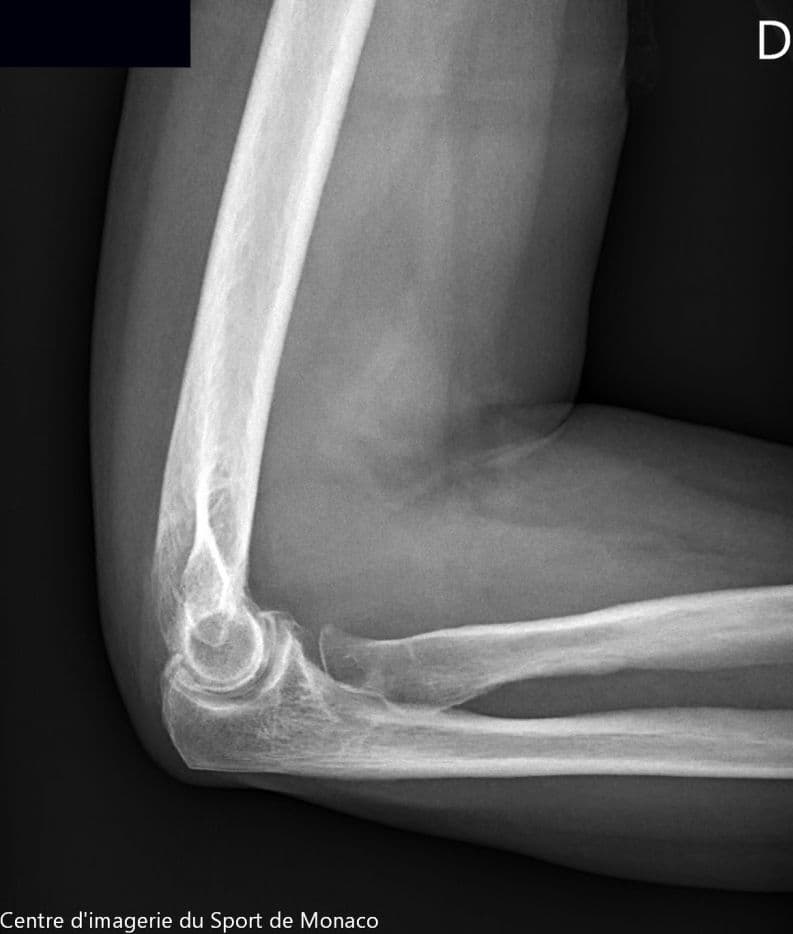

Radiographie

Excroissance osseuse au niveau métaphysoépiphysaire de la tête radiale qui évoque un ostéochondrome à large base d’implantation

Aspect post chirurgical de résection de la tête radiale.